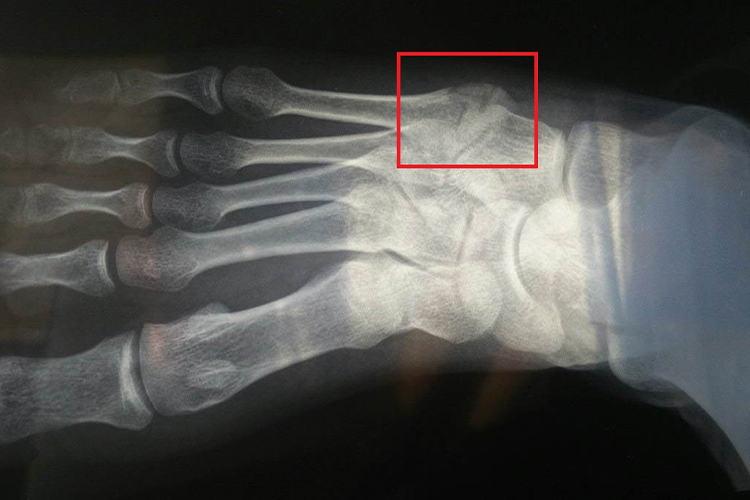

右脚骨裂X光片主要表现为骨裂的裂纹形状、长度、宽度等,伴有疼痛及活动受限,可能与创伤或骨骼疾病等因素有关,需要及时治疗。

右脚骨裂主要表现为骨头上出现裂纹,但并没有出现移位症状,伴有骨裂部位疼痛、肿胀、皮下淤斑等。脚部是身体活动的重要部位,出现骨裂现象后,会导致脚部活动受限。X片上可见骨裂的长度,骨裂的形状,以及骨裂缝隙的大小等。